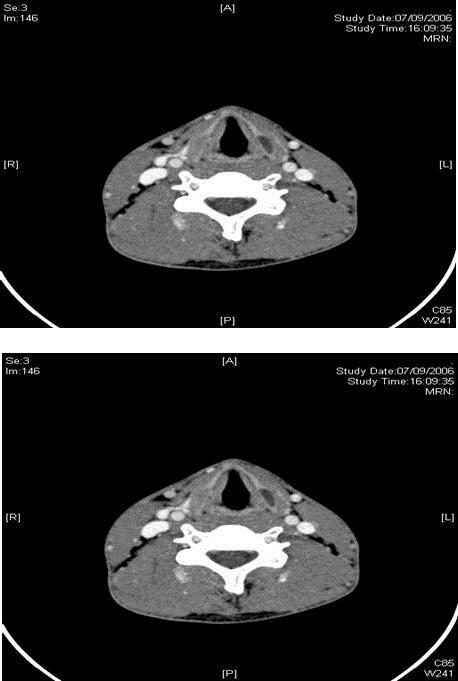

Figure 1.CT scan showing bilateral lamella expansions of the thyroid cartilage with cystic changes on the left

CT scan showing bilateral lamella expansions of the thyroid cartilage with cystic changes on the left